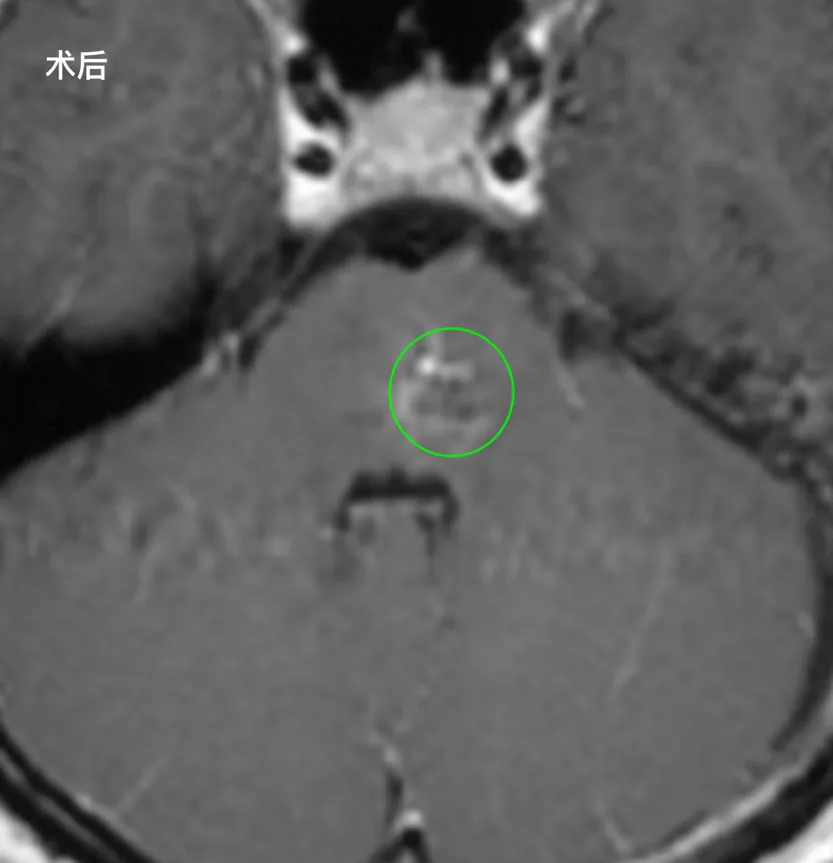

当听到医生说出“手术很顺利,病变也被全切”时,Rita的父母当场红了眼,压在心里的巨石,终于落地了。

术后第1天:Rita在ICU接受脱水、抗炎治疗,生命体征平稳,自主唿吸正常;

术后第2天:复查CT显示颅内无脑水肿、无新发脑出血,她能清晰说话、吞咽正常,顺利转出普通病房;

术后第3天:Rita高兴的发现看东西终于不重影了,在康复师协助下,她第一次下床慢慢走动,开始进行肢体功能锻炼;

术后第10天:伤口拆线愈合良好,症状较术前明显好转,她已经能自主站立行走。

术后3年,Rita同学,视物、肌力完全恢复如常,不仅跟上了学习进度,还以优异成绩通过德国高考Abitur,拿到了心仪大学的录取通知书。